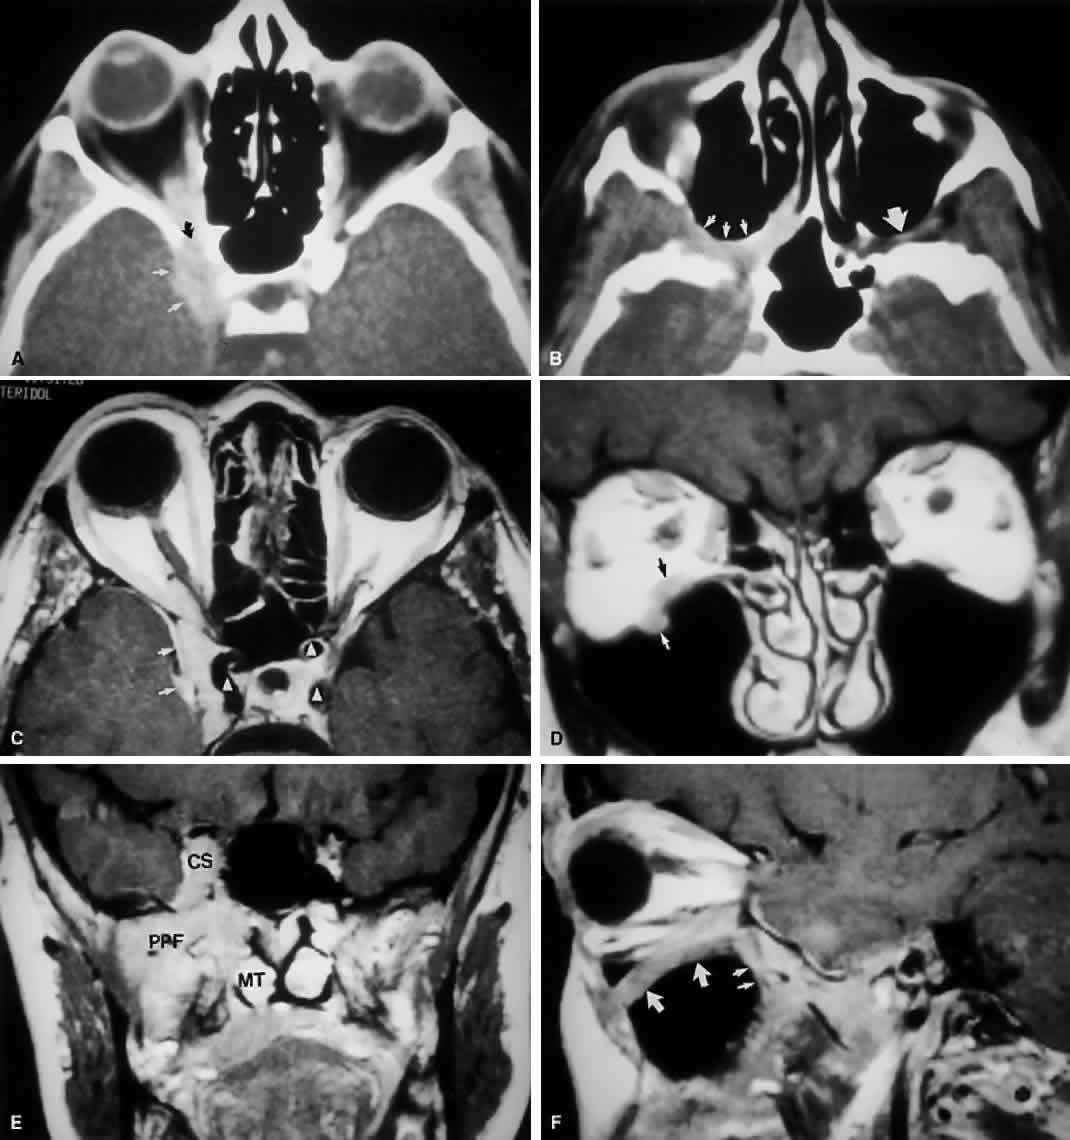

A clear understanding of the relation of the bony orbit to the skull and the midface allows for a logical interpretation of the clinical and radiographic patterns of orbital disease. The bones of the face may be considered to hang from the skull, with attachments at the frontozygomatic and frontoethmoidal sutures, as well as the sphenoid bone. Craniofacial dysjunction occurs in these areas in Le Forte III fractures, and the sites of craniofacial articulation are also the basis for the Le Forte III osteotomies used for facial reconstruction in patients with craniofacial synostoses. The complex shape of the sphenoid wing provides for an intimate communication between the CS, the orbital apex, and the pterygopalatine fossa. Radiographically, the spaces and foramina of the orbital apex may be considered to lie in three tiers (Fig. 8). The CS is found on the same level as the orbital apex, connecting directly with it via the superior orbital fissure (SOF) to form the middle tier. The inferior tier is formed by the inferior orbital fissure (IOF), which provides direct communication between the orbital apex and the pterygopalatine fossa, a vertically oriented space directly behind the maxillary sinus. Finally, the optic canal has no direct communication with any of the aforementioned spaces and should be considered to lie above the SOF and CS, exiting the orbit in a superomedial course through the body of the sphenoid as the superior tier.26 Orbital apical lesions can therefore gain ready access to the CS and pterygopalatine fossa (Fig. 9). Spread into the cranial vault through the optic canal is usually limited to lesions of the optic nerve (glioma) or nerve sheath (meningioma). PARANASAL SINUSES The orbit is surrounded on three sides by the paranasal sinuses (see Fig. 5). The ethmoid sinus runs along the medial orbital wall and is divided into anterior, middle, and posterior air cells by a highly variable system of septa. It is the only sinus to be fully pneumatized at birth. The thin lamina papyracea of the medial orbital wall and the vascular foramina for the anterior and posterior ethmoidal arteries provide scant resistance to the extension of infections and tumors from the ethmoidal sinus to the orbit, even in the adult (Fig. 10). The maxillary sinus borders the orbital floor and is fully pneumatized by 2 to 4 years of age. Unlike the ethmoid sinus, it contains no supporting septa. Although the lamina papyracea is the thinnest of the orbital walls, the network of septations within the ethmoid air cells acts as a supporting scaffolding to the medial orbital wall, much the same way that corrugations strengthen cardboard. Thus, the orbital floor, although not the thinnest wall, is the most frequently fractured, having no underlying support within the maxillary sinus. The posterior wall of the maxillary sinus forms the anterior wall of the pterygopalatine fossa. Frontal sinus pneumatization is highly variable and may continue into the teenage years. Because it drains into the anterior ethmoid air cells, the frontal sinus is often concurrently involved in ethmoid sinus pathology. Supraorbital sinuses are defined as lateral extensions of the ethmoid sinus and span the orbital roof for variable lengths. On occasion, pneumatization to the level of the frontozygomatic suture may occur. Finally, the sphenoid sinus abuts the orbital apex and is the last to pneumatize. Because of the proximity of the optic canal and CS (see Fig. 8), any sphenoid sinus pathology may manifest as a parasellar syndrome (discussed later). Pneumatization of the sphenoid sinus may extend into the anterior clinoid process, a variation of normal anatomy often encountered in orbital imaging studies. FORAMINA AT THE ORBITAL APEX The orbit is generally found to contain nine openings (Table 5). Only the optic foramen, SOF, and IOF will be discussed in detail (see Fig. 8). The optic foramen is located in the medial wall of the orbit in the body and lesser wing of the sphenoid bone. The optic canal is 4 to 10 mm long and 6.5 mm wide. On imaging studies, a 1-mm difference between canal diameters is considered clinically significant. The optic canal transmits the optic nerve, the ophthalmic artery, and the sympathetic innervation to the orbit. Note that sympathetic nerves also travel with the nasociliary nerve via the SOF.

CAVERNOUS SINUS The relation between the CS (Fig. 13) and the orbit is often misunderstood. Briefly, the CS is a venous space located directly behind the SOF and serves as a conduit for most of the motor, sensory, and autonomic nerves that supply the orbit. It is also the major venous drainage for the orbit.3,4 The CS contains the carotid siphon (the S-shaped portion of the internal carotid artery [ICA]), sympathetic fibers closely associated with the carotid artery, cranial nerves III (oculomotor), IV (trochlear), V-1 (ophthalmic division of trigeminal), and VI (abducens), and, as already noted, a venous plexus. The venous plexus communicates with the contralateral CS through an ostium. Parasympathetic fibers also travel through the CS from the Edinger-Westphal nucleus as part of the oculomotor nerve. Remember that a second set of parasympathetics enters the orbit via the sphenopalatine ganglion (see below). In most cases, the maxillary division of the trigeminal nerve (V-2) is closely related to, but not quite within, the posterior and inferior portion of the CS.3,5 SYMPATHETIC AND PARASYMPATHETIC INNERVATION, CILIARY GANGLION Ciliary Ganglion The ciliary ganglion is a flattened, quadrangular structure located deep in the orbit, temporal to the optic nerve and 1 cm anterior to the orbital apex (Fig. 14).28 True ganglion cells and sustentacular or satellite spindle cells, along with the axons of the entering and emerging nerve fibers, form the substance of the ganglion. Rare chemodectomas and primary orbital carcinoids possibly may arise from ciliary ganglion.29–32 Degeneration, trauma, inflammation, or viral infection of the ganglion can cause an efferent (Adie's tonic) pupil; the dissection of the short posterior ciliary nerves necessary to perform optic nerve sheath fenestration often results in a temporary sectoral tonic pupil.33 The ciliary ganglion contains three roots, only one of which actually synapses within the ganglion:

Second, the motor fibers to the EOMs usually enter the inner aspect of each muscle at the junction of the posterior one third and the anterior two thirds of the muscle's length. The exception is the nerve to the inferior oblique, which runs along the lateral aspect of the inferior rectus muscle to enter the inferior oblique muscle near the globe's equator (see Fig. 14). This nerve may be damaged with manipulation of inferior orbital soft tissue during repair of an orbital floor fracture. Because the parasympathetic fibers of the pupil also travel with the nerve to the inferior oblique at the orbital apex, any anterior traction may cause contusion to these more posterior fibers, resulting in a postoperative Adie's pupil.14 VASCULAR SUPPLY Arteries The tissues of the orbit and periorbital region derive their blood supply from two sources—the internal and external carotid arteries.15 Although the majority of orbital blood supply comes from the ICA, anastomoses with external carotid supply are numerous. The ICA enters the calvarium through the foramen lacerum, runs near the posterior clinoid process, and then makes a sharp turn to enter the CS with the abducens nerve (see Fig. 13). As already noted, within the CS the ICA has an S-shaped course called the carotid siphon. As the ICA exits the CS, it gives off its first major intracranial branch, the ophthalmic artery. Before giving off the ophthalmic artery, the ICA has several minor branches that supply the meninges, including the dura of the lateral wall of the CS. An abnormal communication between the arterial and venous supply of the CS results in either a carotid-cavernous fistula or a dural-sinus fistula (Fig. 18A). Because of the larger caliber of the ICA, a carotid-cavernous fistula is usually symptomatic secondary to a high flow state, possibly manifesting as orbital/ocular ischemia and increased intraocular pressure. This type of fistula is most commonly encountered in younger patients after blunt trauma and may require invasive neuroradiologic treatment (Fig. 18B). Conversely, a dural-sinus fistula is typically a low-flow state because the abnormal communication forms between the small-caliber dural arterial feeders of the lateral CS wall and the venous plexus of the CS. Such fistulas are usually seen in older individuals as a spontaneous event. Depending on the severity of symptoms, most dural sinus fistulas are simply followed by observation because of the high rate of spontaneous closure. The ophthalmic artery enters the optic canal inferolateral to the optic nerve, carrying with it a sympathetic plexus from the ICA. The intraorbital course of the ophthalmic artery is highly variable. In about 83% of cases, the artery crosses over the optic canal from lateral to medial and continues to travel superomedially in the orbit to its terminal branches. While still within the orbit, the ophthalmic artery gives off several branches.16 These are most easily subdivided into three groups: ocular, muscular, and extraorbital (Table 12, Fig. 19).